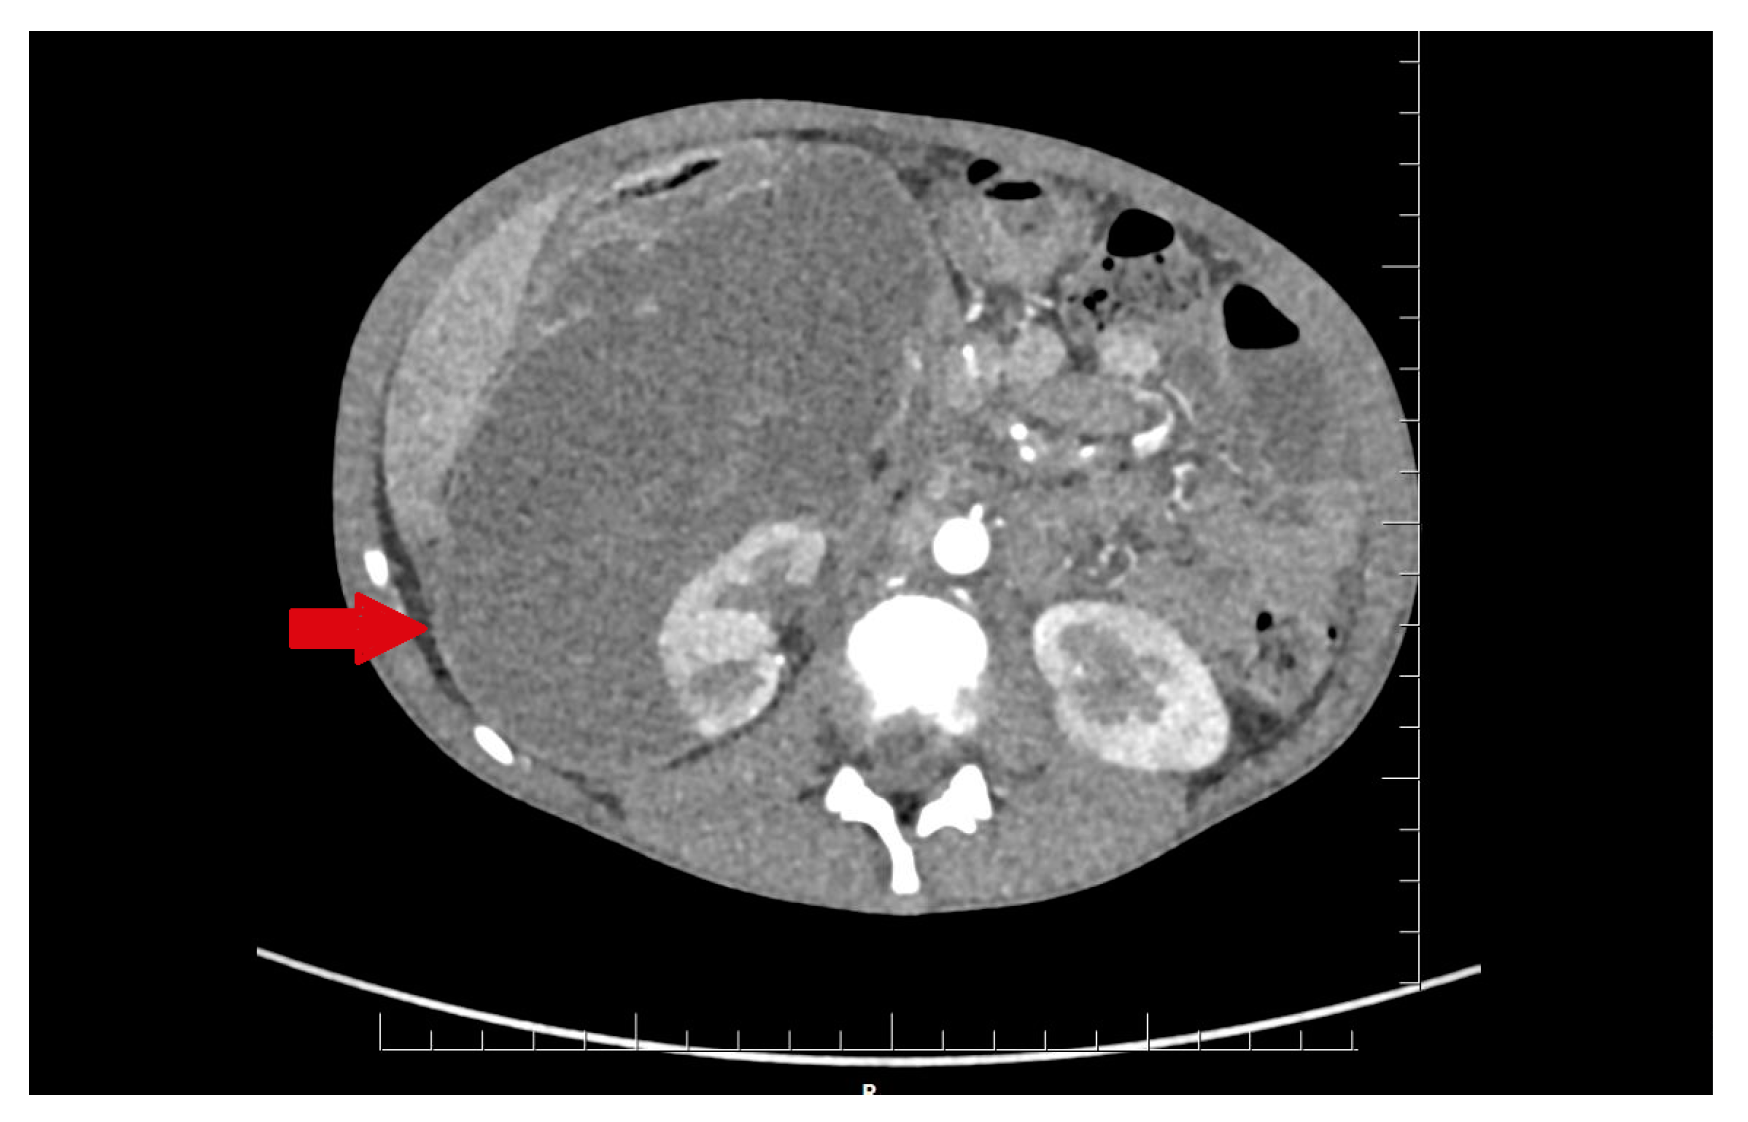

In the infectious disease ward, COVID-19 was excluded. During hospitalization, the patient developed acute abdominal symptoms. The acute condition of the boy appeared suddenly. Results of laboratory tests showed deviations in white blood cells (WBC) = 11.89 × 103/µL, and hemoglobin (HGB) = 6.9 g/dL, with hematocrit (HCT) = 20.6%. The inflammatory markers were elevated. Urinalysis showed 75 mg/dL of proteins. The ultrasound of the abdomen and computed tomography were performed. The diagnosis was unclear. Inflammation, abscess, cyst, and abdominal tumor were suggested. In the computed tomography (CT), the lesion had dimensions: 11.1 × 8.2 × 25 cm (Figure 1 and Figure 2).

It displaced and compressed the inferior vena cava and right renal vein. The lesion adhered to and modeled the liver and pancreas. It was pushing the intestinal loops. The lesion reached down into the bladder. After multidisciplinary consultation with a radiological and oncological team, the decision about surgical treatment was made. Exploratory laparotomy was performed. During the surgery, there was a large amount of purulent content in the peritoneal cavity. A large abscess was visible in the vesicorectal recess. An enormous abscess near the right kidney was localized. The abdominal cavity was thoroughly rinsed. The abdominal cavity and the perirenal space were drained. The bladder was thick and fibrous.

Figure 2. The lesion of unknown character in the area of the right kidney, shown in the frontal plane of the CT scan. The lesion is marked by an arrow.